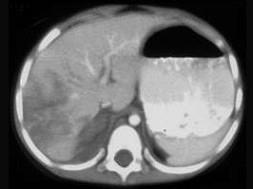

问题 下列图像最佳诊断是 ( )

选项 A、小肠破裂 B、胰腺损伤 C、结肠破裂 D、肝破裂 E、脾破裂

答案 D